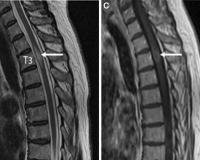

• МРТ спинного мозга. Золотой стандарт» диагностики острого поперечного миелита. Заболевание характеризуется наличием повышенной сигнальной зоны в режиме исследования Т2. Очаг поражения занимает более 2/3 диаметра органа, распространяется на 2 и более сегментов позвоночника. В его центре изредка определяется неизмененная ткань серого вещества.